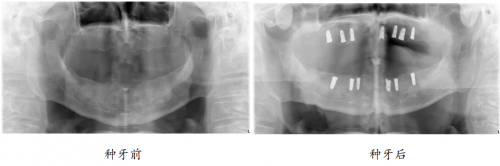

“口福行动”让80岁高龄老人缺牙重生

82岁的孙爷爷,10年前就已全口无牙,一直戴着活动假牙勉强吃饭。

偶然间,在社区举办的“修复失牙·口福行动”公益活动,实现了孙爷爷的种牙梦。

如今种牙1年后,孙叔叔的生活质量得到改善,一日三餐饮食结构丰富,红烧肉、苹果、坚果样样都能轻松消化,“多亏在‘修复失牙·口福行动’公益活动上遇见綦健院长,我现在精气神十足,邻居都说我年轻了10岁。”重获新牙的孙爷爷高兴道。